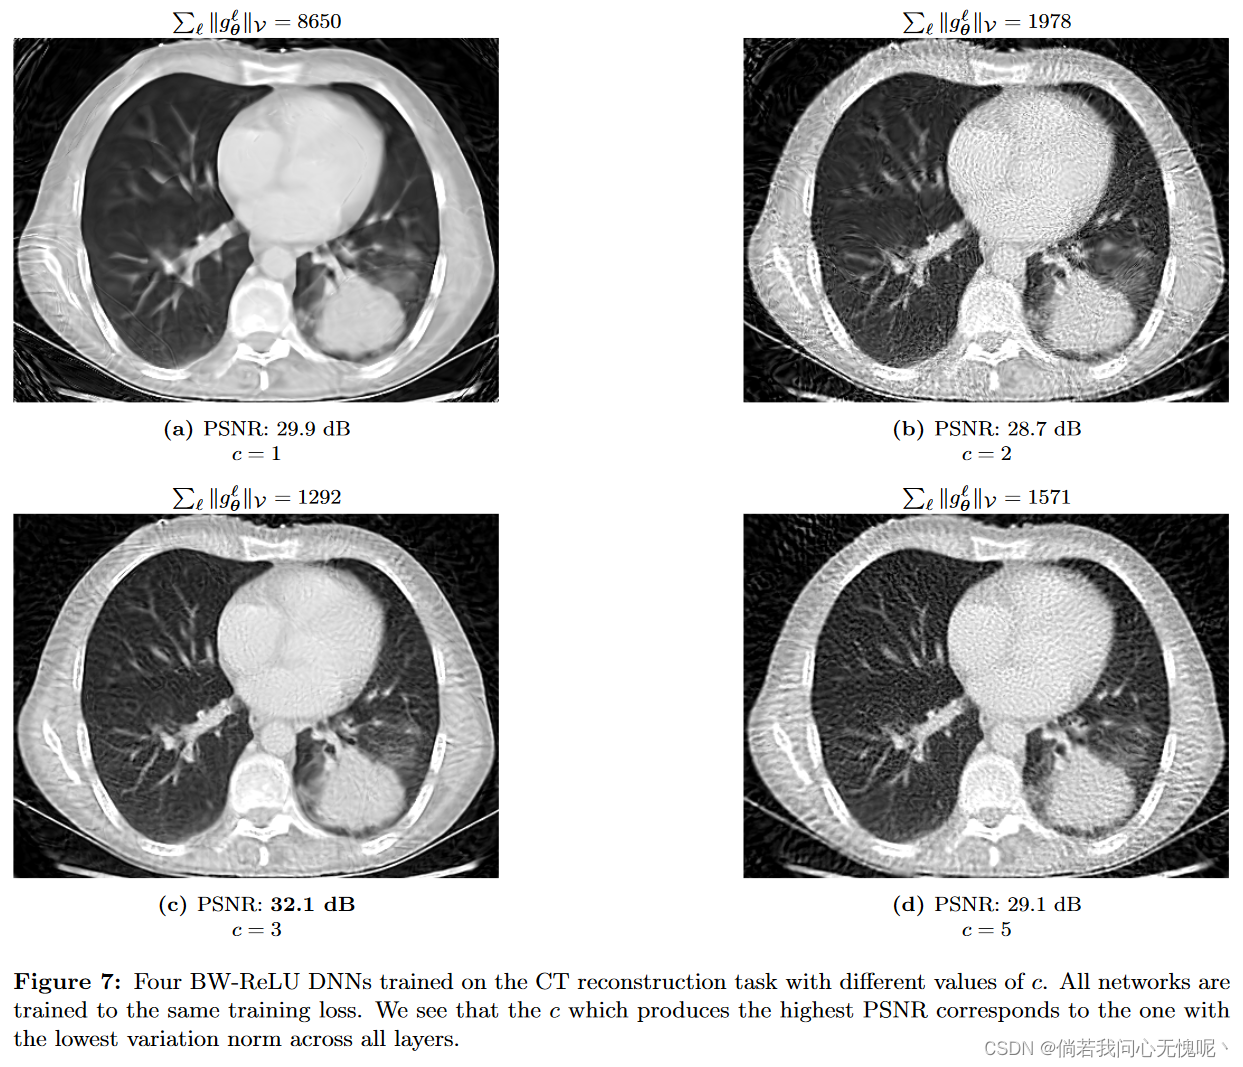

5.4 Low Norm Solutions and Inverse Problems

在我们的最后一个实验中,我们用三个不同的缩放参数训练了BW-ReLU神经网络来完成CT重建任务。在图7中,用于重建图像的三个BW-ReLU神经网络在CT测量数据上获得了相同的训练损失。然而,我们看到,在所有3层中变异范数最小的模型对应于最好的重建。这提出了一种在逆问题中选择尺度参数c的原则性方法。